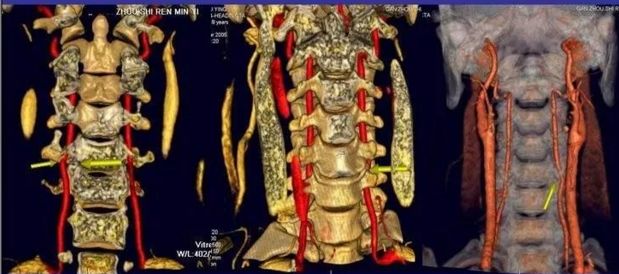

3.椎动脉型颈椎病

当颈椎出现节段性不稳定和椎间隙狭窄时,会造成椎动脉扭曲并受到挤压;骨质增生的形成也可以直接压迫椎动脉、或刺激椎动脉周围的交感神经纤维,使椎动脉痉挛而出现椎动脉血流瞬间变化,导致供血不足而出现症状。

椎动脉型颈椎病是中老年人的常见病。颈椎病患者中约70%有椎动脉受累。50岁以上头晕,头痛者。50%以上与颈椎病引起的椎基底动脉受累有关。

临床表现:

1.眩晕,视物模糊。有时伴随恶心、呕吐、耳鸣或听力下降。

2.下肢可能会突然无力,猝倒,但是意识清醒。

3.偶而也会有肢体麻木、感觉差情况。甚至出现一过性瘫痪,发作性昏迷。(这些都是椎动脉瞬间收到卡压,瞬间造成脑供血缺乏引起的)